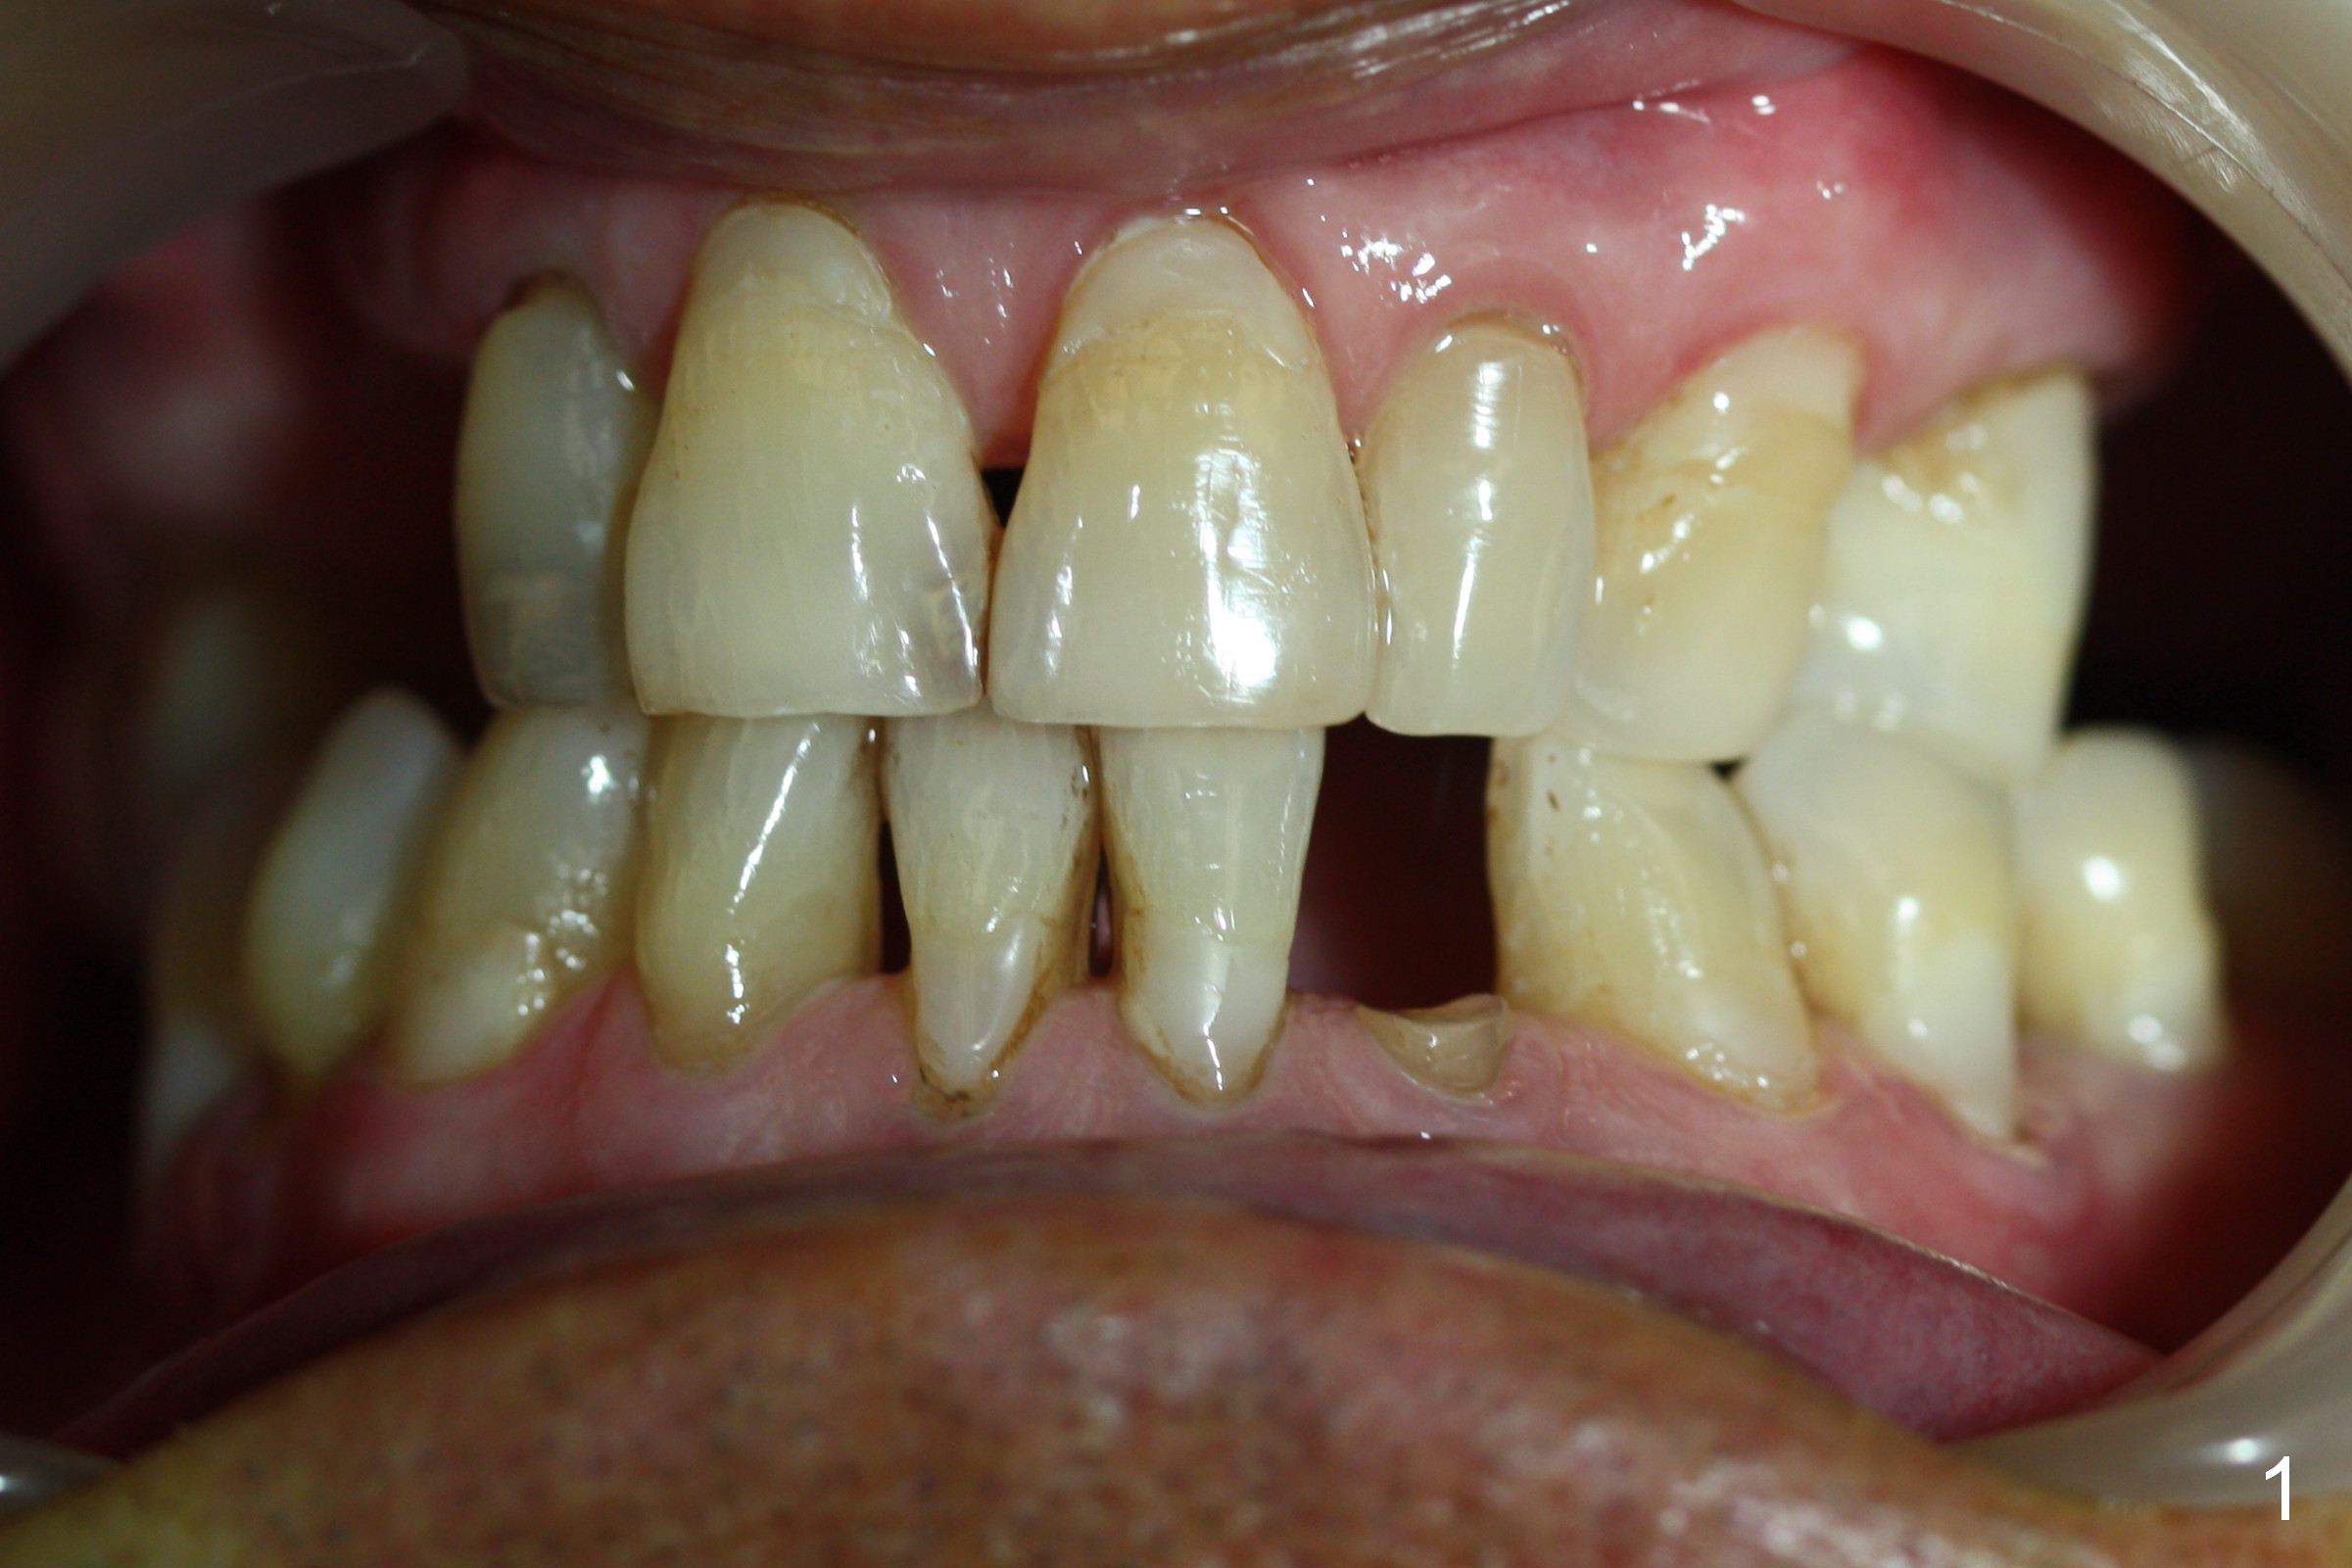

A 74-year-old man has several missing teeth (Fig.1).  His 1st goal is to replace the lower left lateral incisor (Fig.2).  The residual root has an apical lesion (Fig.3 *).  To describe intraop findings, a CT image of a different patient is used (Fig.4 coronal section; B: buccal; L: lingual).  After extraction, the buccal plate is found to be thin and low (Fig.5 arrowheads).  A 1.5 mm pilot drill (Fig.6 red line) is used to initiate osteotomy in the lingual plate of the socket.  Once the drill penetrates the lingual plate, the trajectory changes and the depth is 17 mm from the gingival margin (Fig.7).  A PA is taken (Fig.8); it appears that the osteotomy can be extended more apically.  When the pilot drill extends to 20 mm, there is sudden empty feeling.  The lingual plate has perforated (Fig.9).  A new osteotomy is established buccally (Fig.10 pink).  To avoid buccal plate perforation, especially in the buccal undercut area (>), the coronal end of the drill has to be tilted buccally (<--).  An angled abutment (3x20 mm, 15°) is placed (Fig.11,12).  The abutment is modified (Fig.13,14) to accommodate an immediate provisional (Fig.15,16 P).  Perio dressing is to be applied to prevent the bone graft from getting dislodged buccally (Fig.15).  The dressing is in place 7 days postop (Fig.17).